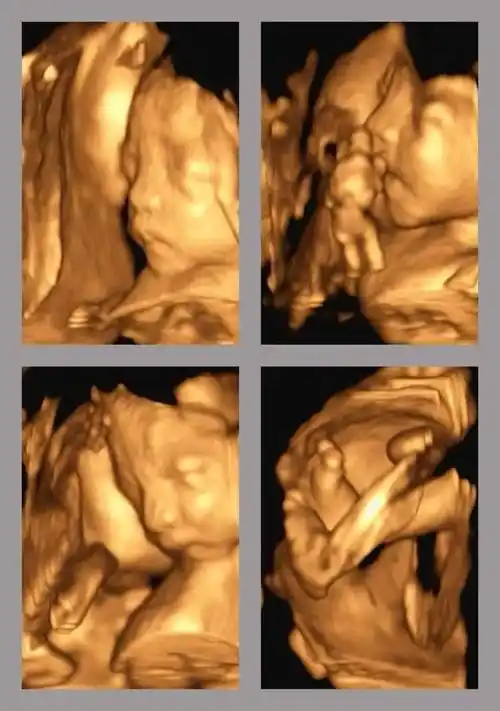

孕11周:生殖器发育(男)怀孕第11周胎儿身长约40毫米,体重约10克,形状

1cm,体重约16.4g,如图所示7070两胎儿的发育情况